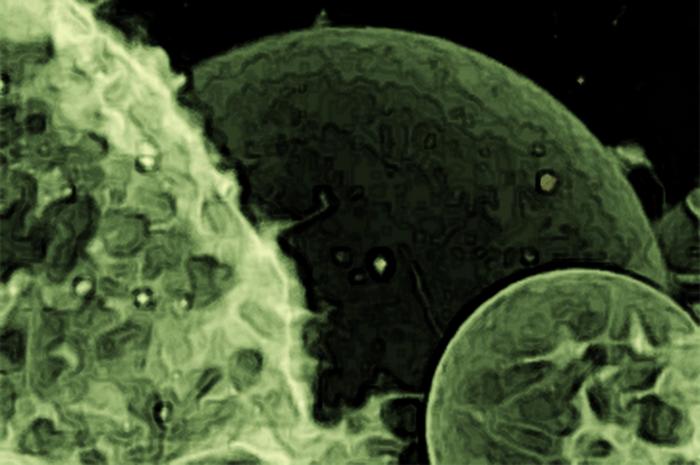

THIS PORTRAIT OF EXTRACELLULAR VESICLES WAS TAKEN USING CONFOCAL LASER SCANNING MICROSCOPY. THE MEMBRANE WAS STAINED WITH FLUORESCENT DYE. IMAGE TITLED “Exosomes” COURTESY OF TOMAŽ EINFALT, UNIVERSITY OF BASEL, UNDER Creative Commons BY-NC-ND license.

Researchers call the tiny brain bubbles under scrutiny in this study small extracellular vesicles (sEVs). These tiny biological water balloons are produced by most cells in the body to ferry a wide variety of proteins, lipids and byproducts of cellular metabolism, as well as RNA nucleic acid codes used by recipient cells to construct new proteins.